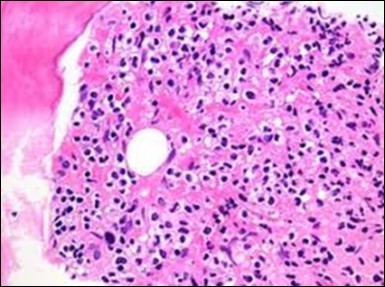

Figure 1.HCL: hairy cells infiltrating designated spaces(17).

The leukaemia cells may enunciate a characteristic immune phenotype, crucial for a confirmatory diagnosis. The peripheral blood mononuclear B cell population may display a kappa or lambda light chain restriction. The phenotype of classic hairy cell leukaemia may be delineated by concurrent, immune reactive CD19+ CD20+,CD 11c+, CD25+, CD103+ and CD123+. An intensely immune reactive CD200+ and a non reactive CD27- antigen may be present2, 4. Evaluation of a trephine bone marrow biopsy and bone marrow aspirate may define the degree of tumour infiltration. A dry tap on account of prominent bone marrow fibrosis may be elucidated at preliminary diagnosis. A decline in the normal haematopoiesis may account for a hypo-cellular marrow in 10% instances. Gradation of cellular infiltrating of the leukaemia within the bone marrow may be appropriately investigated with immune –histochemical stains2, 4. Immune staining for CD20+, annexin 1 and VE1 (a BRAF V600E stain] may validate the diagnosis and precisely analyse the extent of malignant bone marrow infiltration[8]. Determination of BRAF V600E mutation may be critical in therapeutically non responsive individuals with applicable standard therapy or in instances of multitudinous reoccurrences[9]. Deploying inhibitors of BRAF V600E gene may be efficacious in patients impervious to approved therapy. The mutation necessitates a comprehensive scrutiny of the implicated individuals with a sensitive molecular assay which may discern up to < 10% of the hairy leukaemia cells appearing in the peripheral blood smears or bone marrow aspirates diluted with peripheral blood or aspirates elucidating a dry tap[2,4]. Allele specific polymerase chain reaction (PCR) or a next generation sequencing may be optimally employed to circumvent false negative outcomes. If the leukaemia cells are sparse or if particularly sensitive & efficacious molecular techniques are not accessible, the application of appropriate immune histochemical stains to the bone marrow biopsy such as a BRAF V600E mutation stain (VE1) may detect the hairy cells and conclusively diagnose the condition[2,4,10]. Figure 1, Figure 2, Figure 3, Figure 4, Figure 5, Figure 6, Figure 7, Figure 8, Figure 9, Figure 10, Figure 11, Figure 12, Figure 13, Figure 14.

The classic hairy cell is medium sized with a magnitude of 10-14µm. The moderately abundant or variable cytoplasm may be transparent or mildly basophilic. The cellular surface with the characteristic serrated perimeter depicts innumerable fragile or stout extensions of cytoplasm ,particularly discernible on the phase contrast and electron microscopy. The cytoplasm may exhibit vacuoles with occasional azurophilic granules4. The nucleus may be elliptical or reniform, folded or indented with a coarse, reticulated or a finely dispersed chromatin and inconspicuous nucleoli along with infrequent mitosis. Bone marrow aspiration or bone marrow trephine biopsy may be inadequate for diagnosis in 30%-50% individuals4. The trephine sections of the bone marrow may depict a characteristic interstitial pattern of leukaemic infiltration. Generally the bone marrow is hyper-cellular, though it may be hypo-cellular in 10-15% individuals4. The leukaemia cell ingress may be diffuse or partial, although diffuse infiltration is frequent. The partial variety of leukaemic dissemination may be ineptly categorized with an indeterminate differentiation from the uninvolved marrow. The malignant insertions may initially emerge as miniature, undefined, cellular loci. The formalin fixed, paraffin embedded sections may elucidate a crystalline zone or a “halo” appearance of the cells with a circumscribed nucleus on account of the plentiful cytoplasm4. The cellular margins may be intertwined. Fixation of bone marrow smears with Zenker’s fixative may demonstrate a retracted cytoplasm of the hairy cells with a consequent disconnected structure. The bone marrow in the absence of a malignant process may be hypo-cellular or hyper-cellular. Reticulin stains may delineate an enhanced accrual of broad, dense reticulum fibres surrounding the aggregates of leukaemia cells with the fibrous circumlocution of individual malignant cell and fibrotic extensions into the abutting, uninvolved bone marrow4.